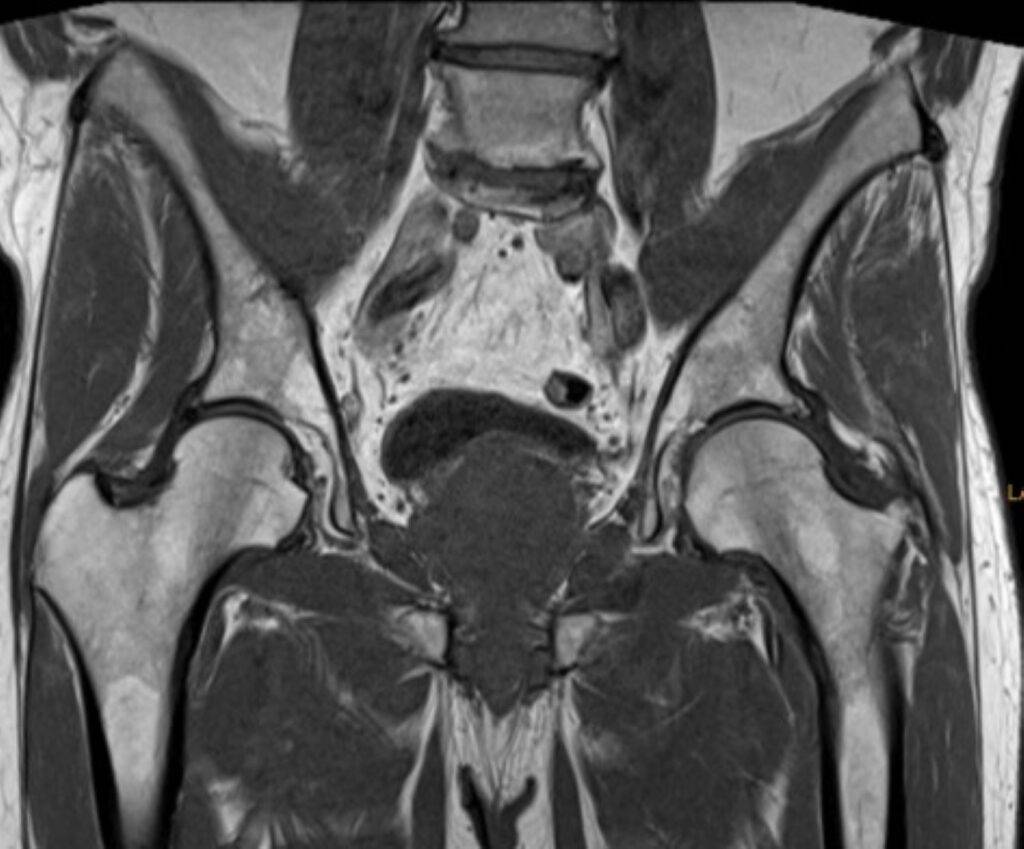

Man unterscheidet zwischen: MRT des knöchernen Beckens, MRT des weiblichen Beckens, sowie einer MRT Prostata

• Beckenknochen: Der Knochen des Beckens wird einschließlich des Beckenrings, Kreuzbeins und der Hüftgelenke detailliert dargestellt. Insbesondere bei Arthrose in der Hüfte ist dies hilfreich.

Das knöcherne Becken besteht aus den beiden Hüftknochen (Ossa coxae) und dem Kreuzbein (Os sacrum), die zusammen den sogenannten Beckengürtel bilden. Hinten (dorsal) sind die Hüftknochen über kaum bewegliche Gelenke sehr fest mit dem Kreuzbein verbunden. Vorne (ventral) stehen die beiden Hüftknochen über die Schambeinfuge in Kontakt. Die Schambeinfuge ist eine knorpelige Verbindung.

Unser knöchernes Becken kann in zwei Abschnitte unterteilt werden: das große Becken oberhalb der sogenannten Beckeneingangslinie und das kleine Becken unterhalb dieser Linie. Das große Becken enthält Teile des Dünn- und Dickdarms, während sich im kleinen Becken bei Frauen der Mastdarm, die Harnblase, die Eierstöcke, die Gebärmutter und die Vagina und bei Männern die Prostata befindet.

Knochen, Gelenke, Muskeln und Organe des Beckens können mittels MRT ohne Strahlenbelastung dargestellt werden. Auf diese Weise können verschiedenste Veränderungen oder Verletzungen erkannt und beurteilt werden.